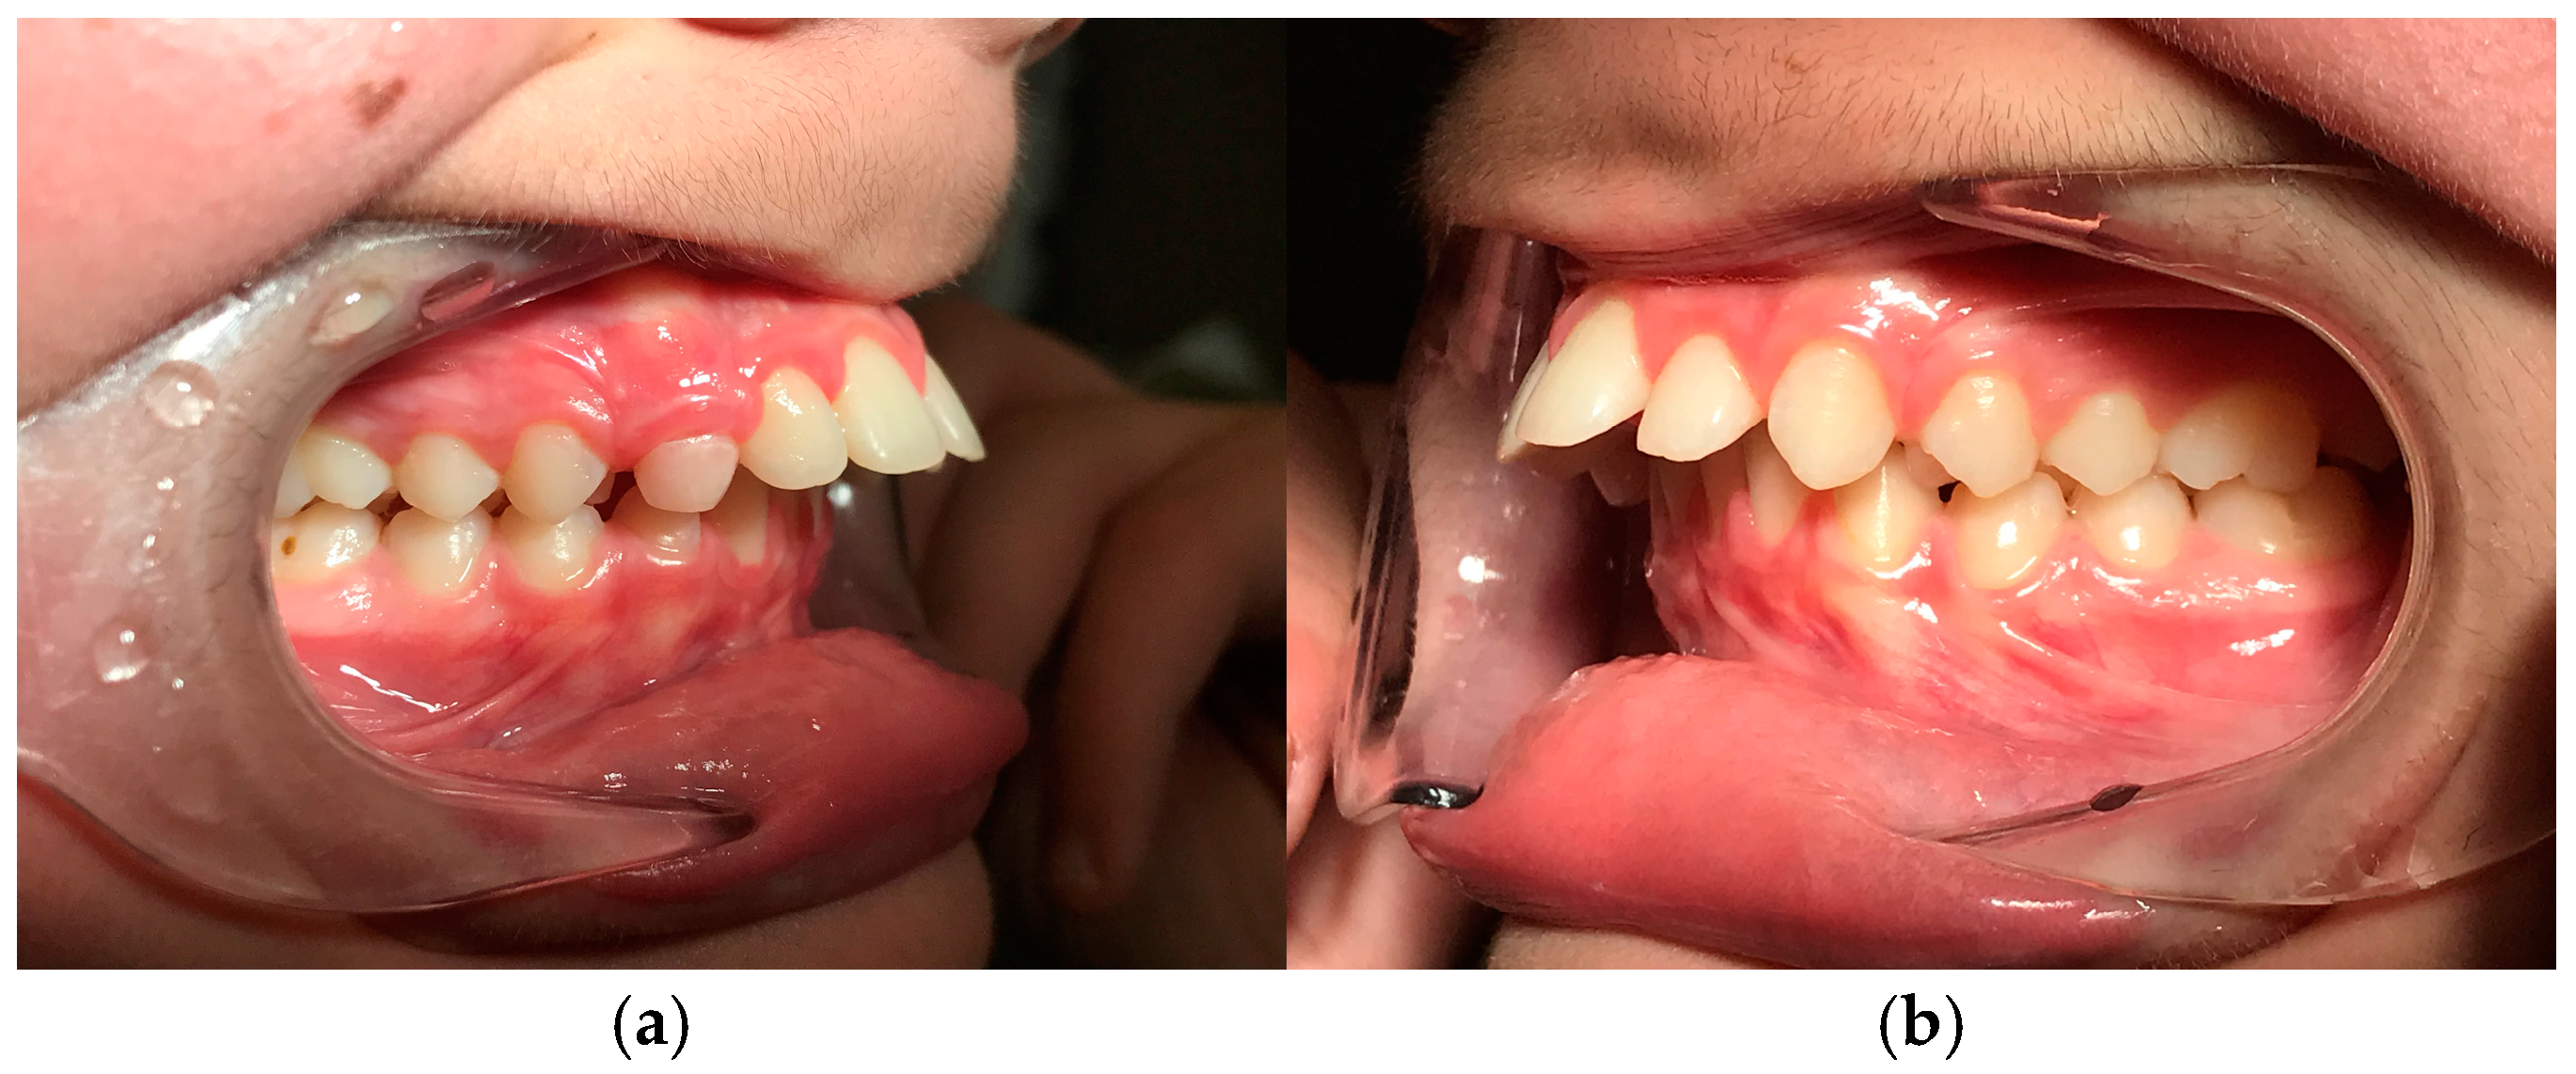

2.5. Case Report Throughout Clinical Phases

The following is a case in which the simplified model and the sequence of clinical phases were used. In our clinical practice, the treatment begins with a phase of alignment and leveling of the arches, elimination of the excessive pro-inclination of the incisors (for example in the case of diastemas as visible in photo (

Figure 2a,b), coordination of the arches through coordinated final steel arches; coordination is checked clinically by manually guiding the patient and asking for the positioning of the protruding mandible with contact of the incisal edges with approximately 2 mm of overjet.